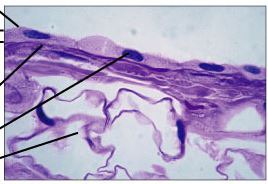

keratinization

Process of hardening, dehydration, and keratin accumulation that occurs in epidermal cells as they migrate outward

stratum corneum

dermis

Inner layer of skin, binds epidermis to underlying tissues